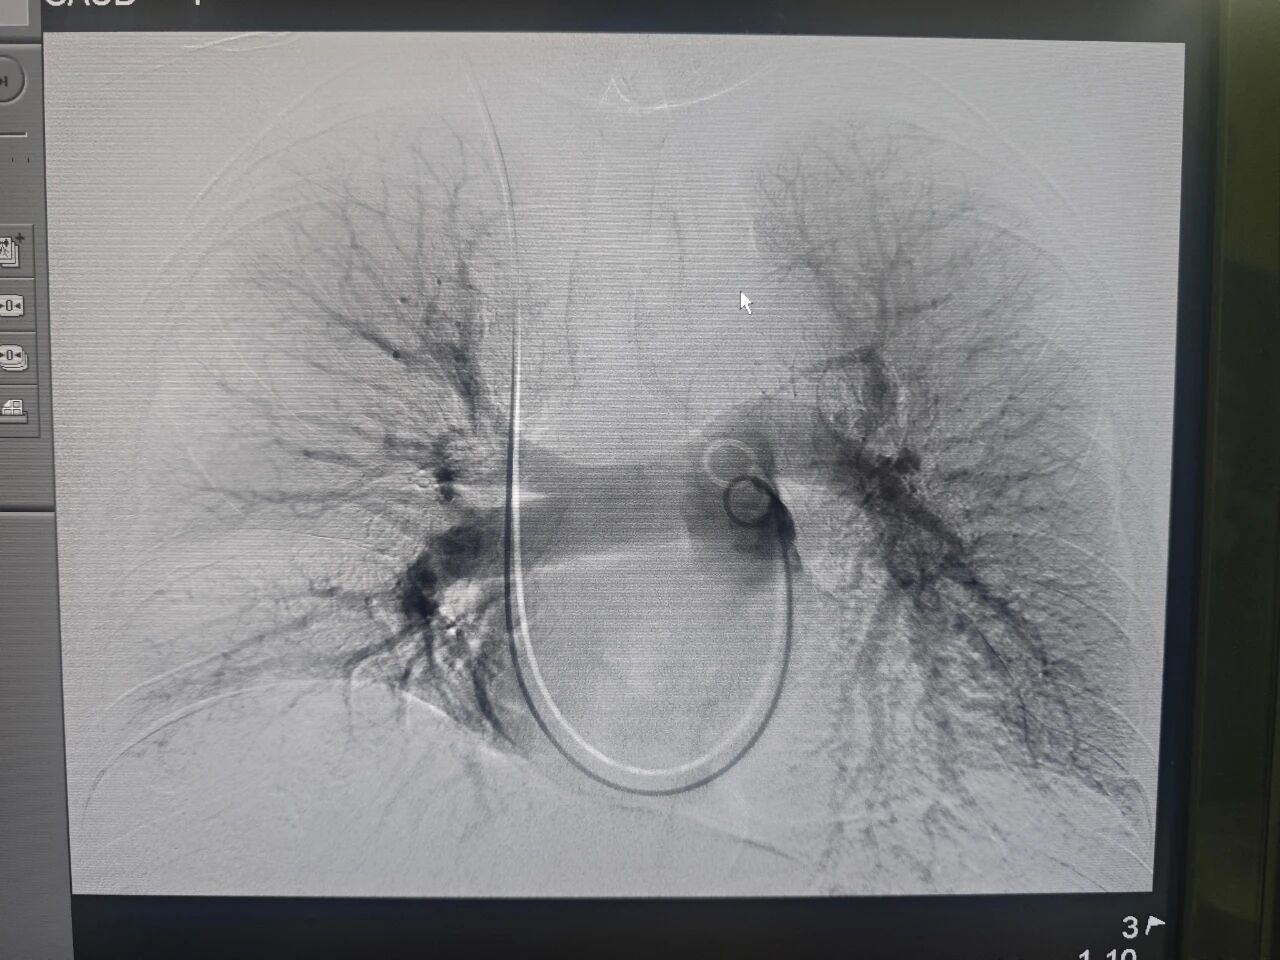

在充分的术前准备后,介入科主任陈龙与副主任王培振共同为吴医生施行了“下肢静脉造影+肺动脉造影术及肺动脉血栓溶解剂灌注术”。手术经由右颈部穿刺,导管精准抵达肺动脉,造影显示双侧肺动脉分支存在多处充盈缺损(血栓)。手术团队成功留置溶栓导管,过程十分顺利,术后安返病房。

术后三天复查造影显示,吴医生肺动脉血流恢复通畅,手术效果良好。溶栓导管拔除后,穿刺部位仅有不足1厘米的微小创口。目前,吴医生在介入科医护人员精心照护下,康复情况良好。